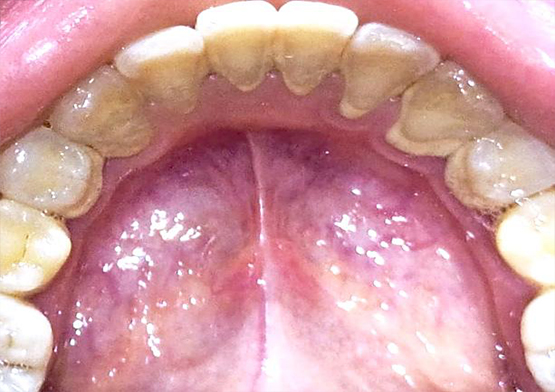

Hasil Scaling di Poli Gigi Alkindi

Before